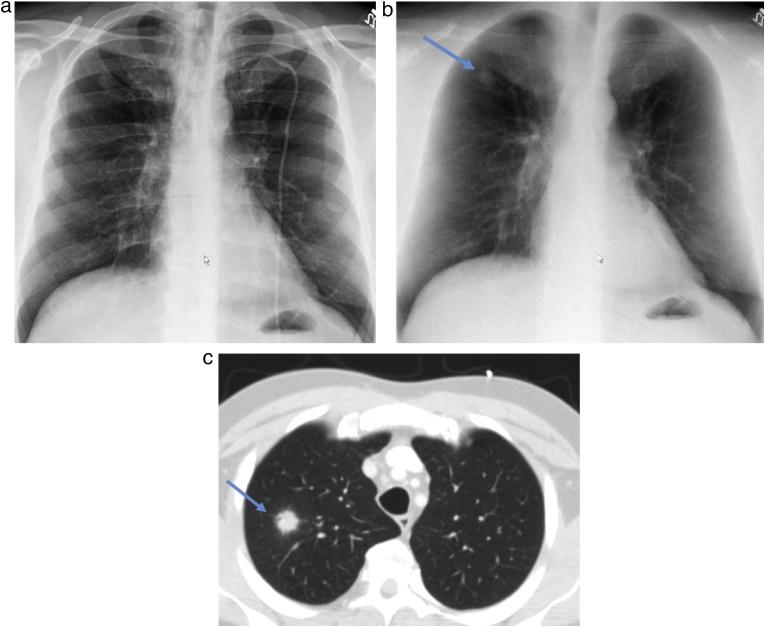

Recent advances in dual-energy imaging techniques, dual-energy subtraction radiography (DESR) and dual-energy CT (DECT), offer new and useful additional information to conventional imaging, thus improving assessment of cardiothoracic abnormalities. DESR facilitates detection and characterization of pulmonary nodules. Other advantages of DESR include better depiction of pleural, lung parenchymal, airway and chest wall abnormalities, detection of foreign bodies and indwelling devices, improved visualization of cardiac and coronary artery calcifications helping in risk stratification of coronary artery disease, and diagnosing conditions like constrictive pericarditis and valvular stenosis. Commercially available DECT approaches are classified into emission based (dual rotation/spin, dual source, rapid kilovoltage switching and split beam) and detector-based (dual layer) systems. DECT provide several specialized image reconstructions. Virtual non-contrast images (VNC) allow for radiation dose reduction by obviating need for true non contrast images, low energy virtual mono-energetic images (VMI) boost contrast enhancement and help in salvaging otherwise non-diagnostic vascular studies, high energy VMI reduce beam hardening artifacts from metallic hardware or dense contrast material, and iodine density images allow quantitative and qualitative assessment of enhancement/iodine distribution. The large amount of data generated by DECT can affect interpreting physician efficiency but also limit clinical adoption of the technology. Optimization of the existing workflow and streamlining the integration between post-processing software and picture archiving and communication system (PACS) is therefore warranted.

双能成像技术的最新进展,即双能减影X线摄影(DESR)和双能CT(DECT),为传统成像提供了新的有用的附加信息,从而改善了对心胸异常的评估。DESR有助于肺结节的检测和特征描述。DESR的其他优点包括能更好地显示胸膜、肺实质、气道和胸壁异常,检测异物和植入装置,改善心脏和冠状动脉钙化的可视化,有助于冠状动脉疾病的风险分层,以及诊断缩窄性心包炎和瓣膜狭窄等疾病。市售的DECT方法分为基于发射的(双旋转/自旋、双源、快速千伏切换和分束)和基于探测器的(双层)系统。DECT提供几种专门的图像重建。虚拟非增强图像(VNC)通过消除对真正非增强图像的需求来降低辐射剂量,低能量虚拟单能图像(VMI)增强对比度,有助于挽救原本无法诊断的血管研究,高能量VMI减少金属硬件或高密度对比剂引起的线束硬化伪影,碘密度图像允许对增强/碘分布进行定量和定性评估。DECT产生的大量数据可能会影响解读医生的效率,但也限制了该技术在临床上的应用。因此,有必要优化现有的工作流程,并简化后处理软件与图像存档和通信系统(PACS)之间的集成。